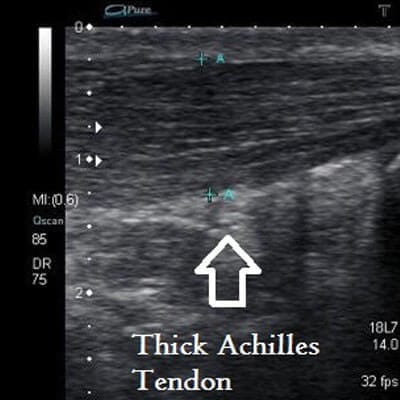

Midportion Achilles Tendinopathy

Insertional Achilles Tendon

Ultrasound is beneficial in diagnosis of soft tissue injuries including Plantar Fasciitis, Achilles Tendinopathy, Forefoot pathology, Ankle sprain